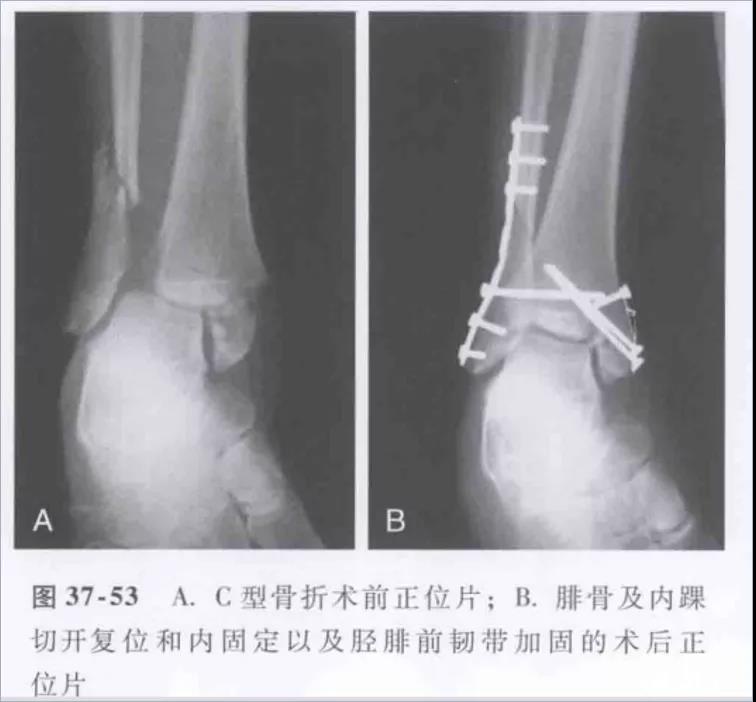

踝关节骨折分型-Weber——WeberA型-韧带下——WeberB型-经韧带——WeberC型-韧带上

Lauge-Hansen-旋前外旋(PE)受伤时,足处于旋前背伸外展位,距骨外旋。Ⅰ:三角韧带紧张,造成三角韧带损伤或者是内踝撕脱性骨折。Ⅱ°:外力继续作用,距骨外旋造成下胫腓前韧带和骨间韧带损伤,或者韧带附着点撕脱性骨折。Ⅲ°:外力继续作用,腓骨受到向外向后的旋转应力,造成腓骨的螺旋性骨折(特点:腓骨由于足本身的位置,外旋力大,向上传导,骨折位于下联合上方,甚至可以达到腓骨颈部位- Maisonneuve骨折)。Ⅳ:外力继续作用,下胫腓后韧带紧张,造成下胫腓后韧带断裂或后踝撕脱骨折。